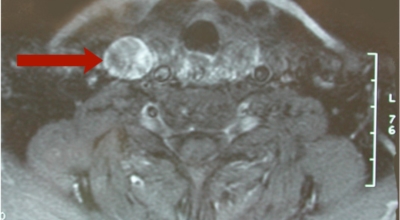

갑상선 초음파를 통하여 크기와 위치를 확인됐습니다. 미세침흡인세포검사라는 검사를 통하여 수술 전에 갑상선암을 알아낼 수 있어요. 또한, 혈액 검사를 통하여 갑상선 기능을 알아낼 수 있다고 하며, 갑상선 수질암의 경우 칼시토닌의 증가로 질병을 알아낼 수 있어요. 크기가 1cm 아래로 작은 갑상선암은 간단한 초음파 검사만으로도 추적하여 검사를 할 수 있어요. 1cm 이하의 크기를 지니고 있는 작은 갑상선암을 수술로 제거하게 되면, 갑상선염절제술이면 충분하게 갑상선암을 절제할 수 있어요. 재발의 염려를 가지고 있는 갑상선암의 경우에는 갑상선 전절제술을 받는 것이 좋고, 삶의 질을 고려하게 된다면 반절제술을 진행하는 게 좋아요.